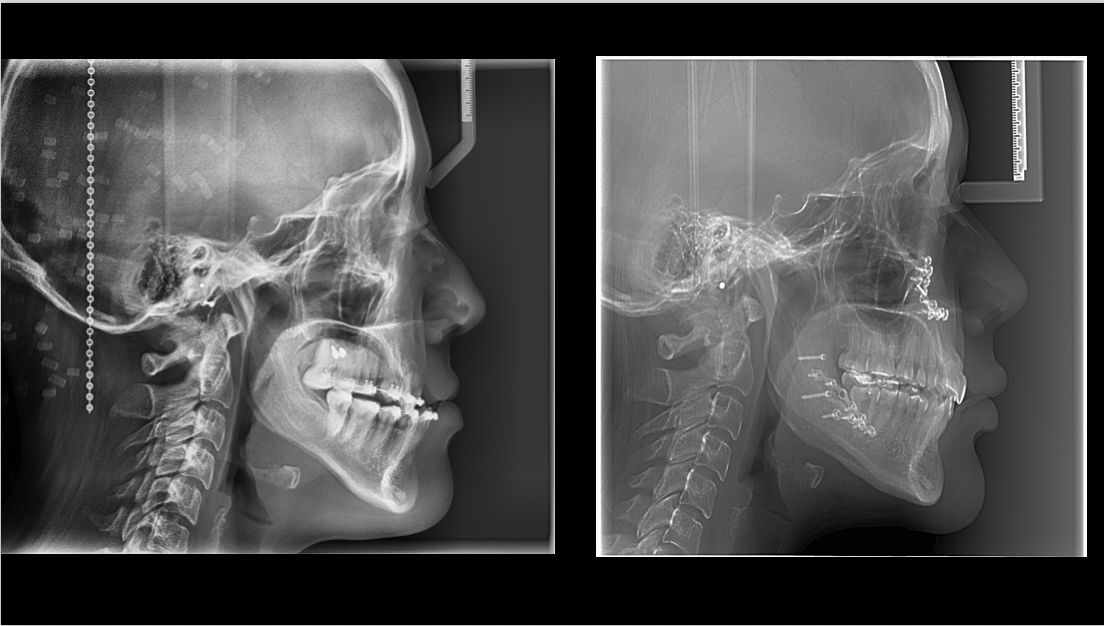

¡Hola! Soy el Dr. Emmanuel Guerrero Soto, Cirujano Oral y Maxilofacial con Mención Honorífica por el Hospital Central Militar, Master en Cirugía Ortognática por la Universidad Francisco de Vitoria de Madrid, España, Fellow también en Cirugia Ortognática por parte de Ortognatica Roma, Italia; y Fellow en Implantología Quirúrgica con estudios en Vitoria, España. Conmigo tendrás un trato humano, paciente y efectivo. Para conocer más sobre nuestro trabajo y ubicaciones, visita nuestra pagina de Instagram.

- Cirugía ortognática y estética

Experto en Ortognática e Implantes dentalesMaster/Fellow Internacional en Cirugía Ortognática+10 años de experiencia extrayendo 3ros molares